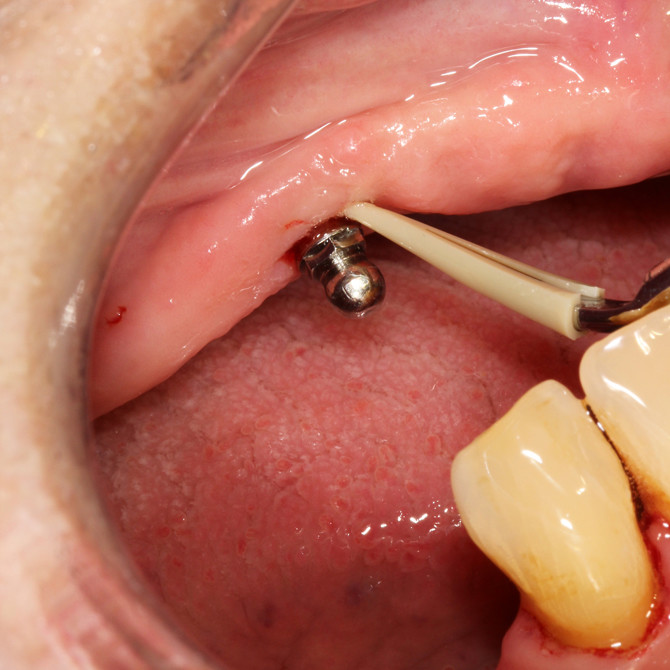

Metallfreier Spezial Aufsatz aus hochwertigem Kunststoff (PEEK) entfernt mühelos Plaque und Zahnstein von Implantatoberflächen und Restaurationen aus Metall oder Keramik

Keine Beschädigung oder Abrasion von Titanoberflächen

Reinigung unter Spülung und Speichelabsaugung

Ultraschallaufsatz OHNE Spezial Kunststoffspitze – zur supragingivalen Entfernung von Konkrementen MIT Spezial Kunststoffspitze – für die schonende Implantatprophylaxe